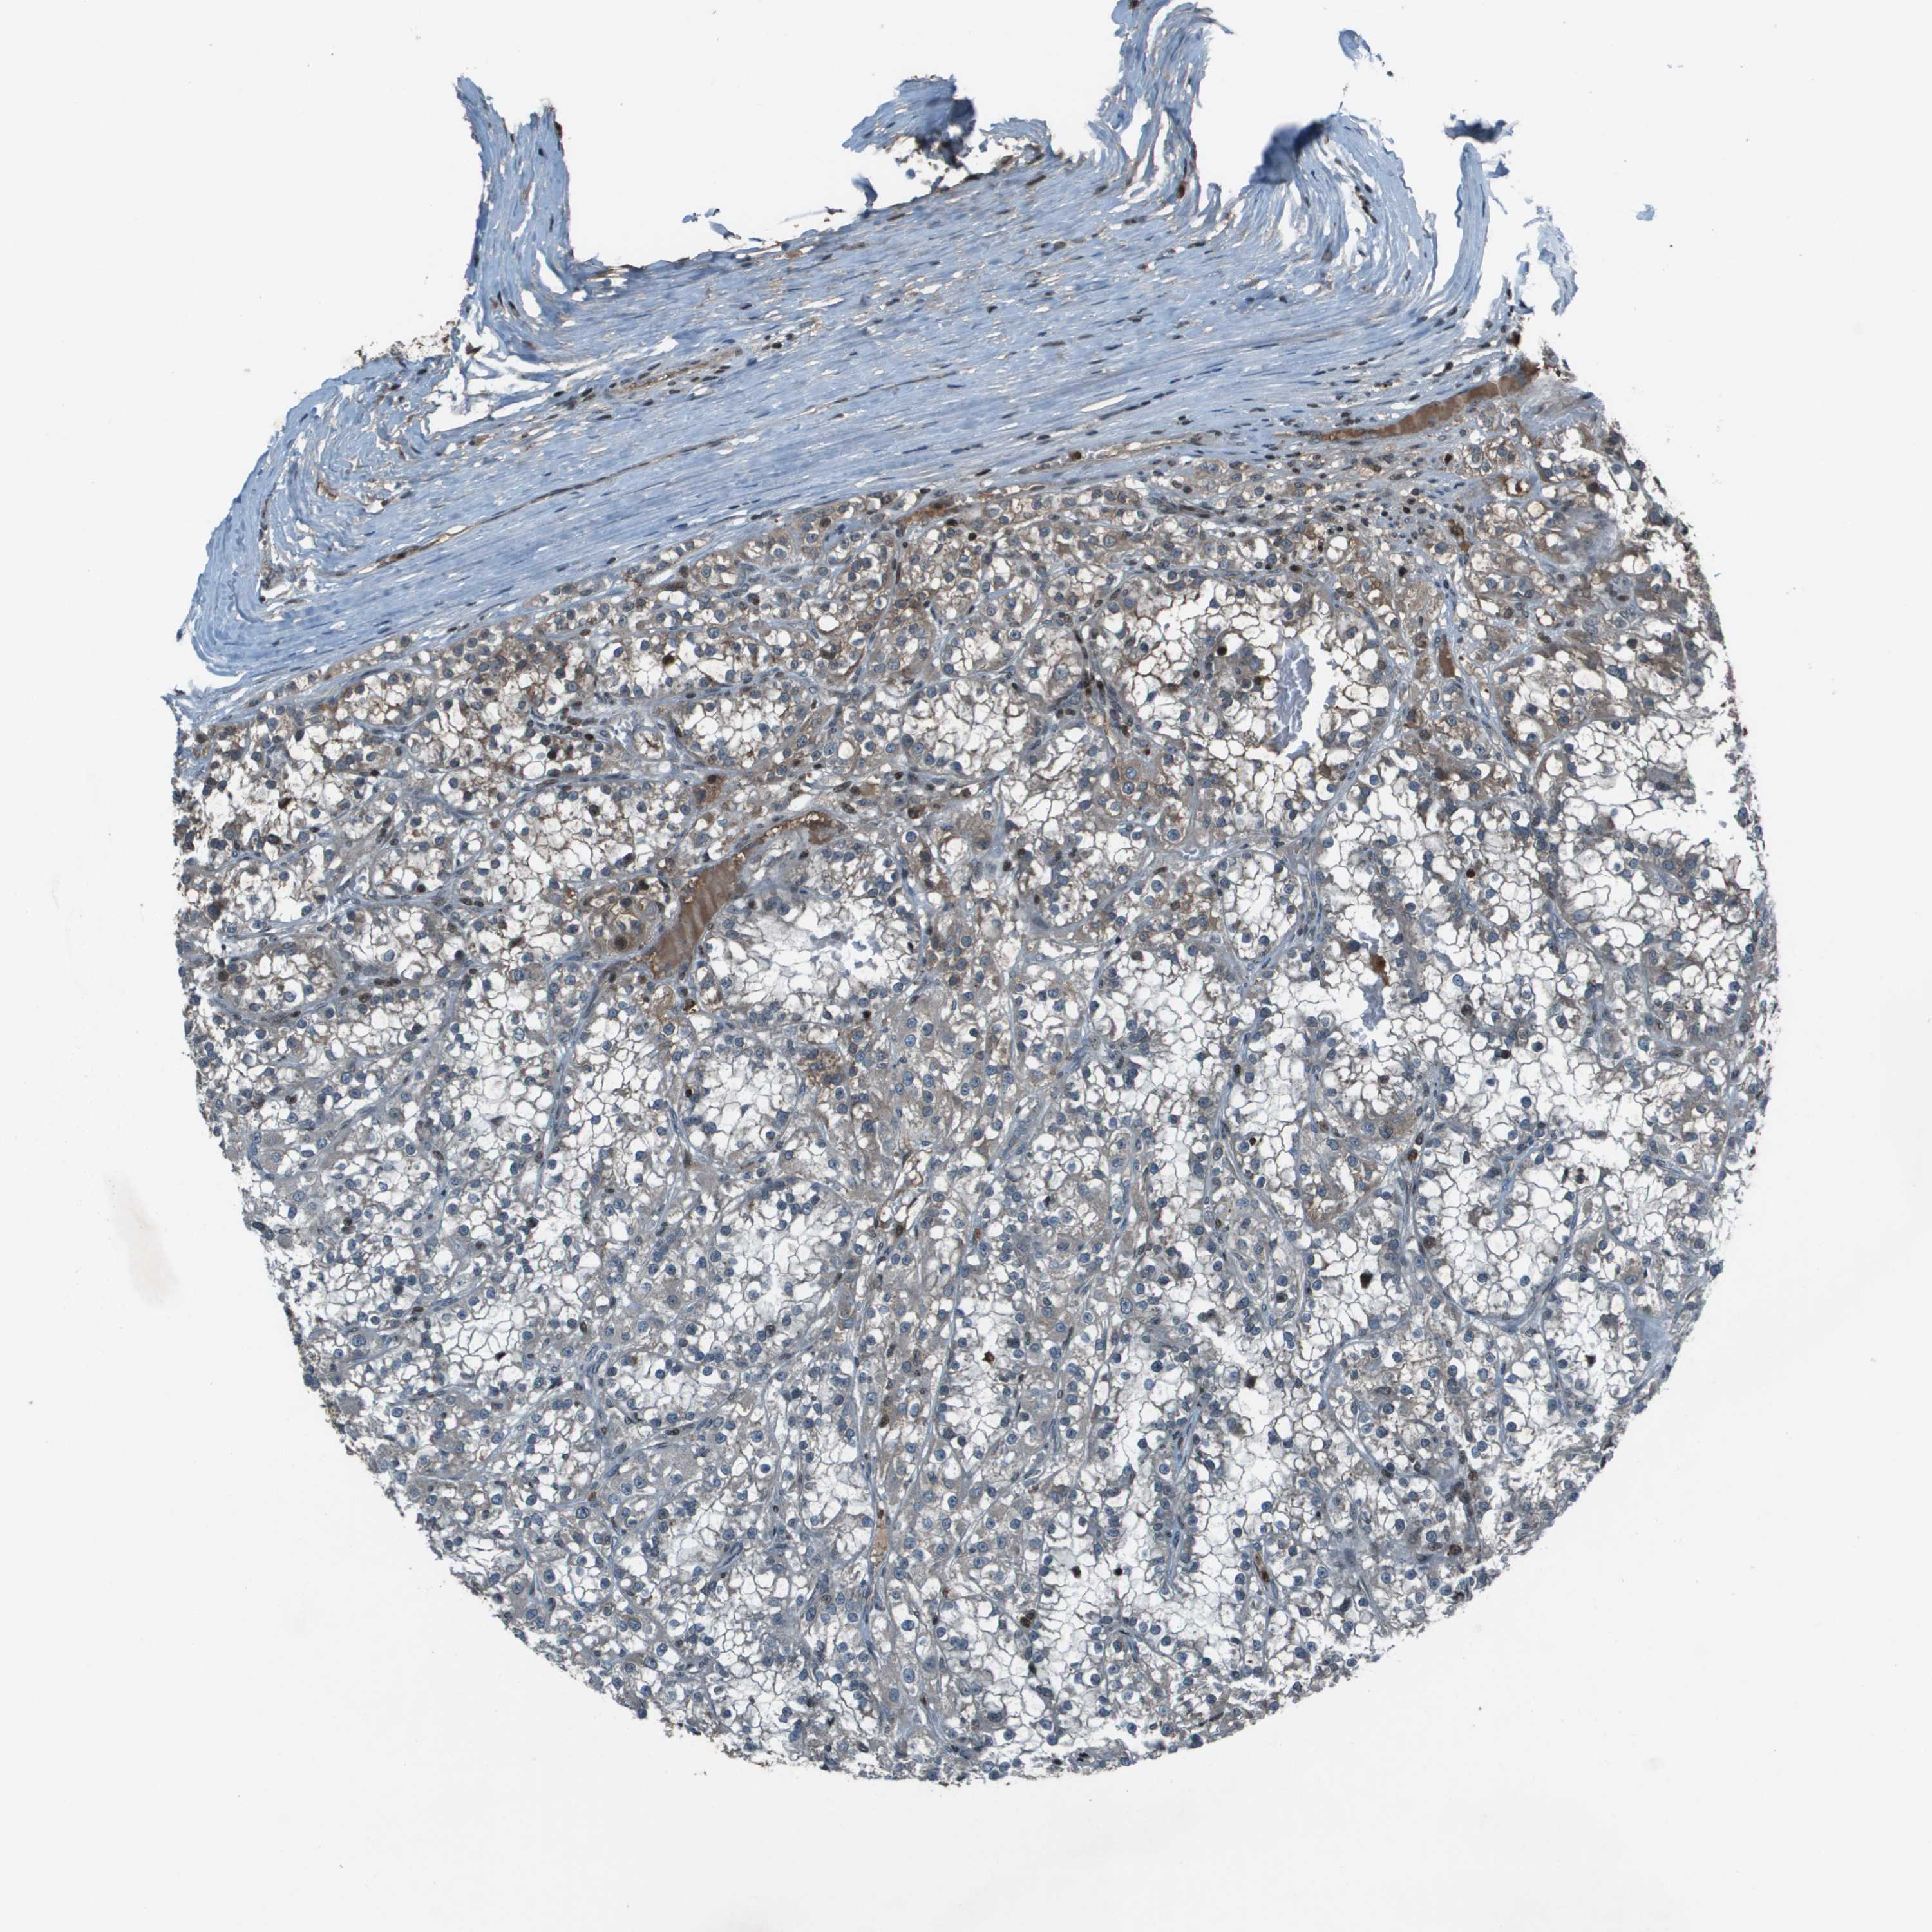

KIDNEY RENAL CLEAR CELL CARCINOMA (VALIDATION) - Interactive survival scatter ploti

The Survival Scatter plot shows the clinical status (i.e. dead or alive) for all individuals in the patient cohort, based on the same data that underlies the corresponding Kaplan-Meier plots. Patients that are alive at last time for follow-up are shown in blue and patients who have died during the study are shown in red.

The x-axis shows the expression levels (FPKM) of the investigated gene in the tumor tissue at the time of diagnosis. The y-axis shows the follow-up time after diagnosis (years). Both axes are complimented with kernel density curves demonstrating the data density over the axes. The top density plot shows the expression levels (FPKM) distribution among dead (red) and alive patients (blue). The right density plot shows the data density of the survived years of dead patients with high and low expression levels respectively, stratified using the cutoff indicated by the vertical dashed line through the Survival Scatter plot. This cutoff is automatically defined based on the FPKM cutoff that minimizes the p-score. The cutoff can be changed by dragging the vertical line or by entering a cutoff value in the square labeled "Current cut-off".

Under the Survival Scatter plot the p-score landscape (black curve; left axis) is shown together with dead median separation (red curve; right axis). Dead median separation is the difference in median mRNA expression between patients who have died with high and low expression, respectively. It is calculated as follows: median FPKM expression of dead patients with high expression - median FPKM expression of dead patients with low expression. This is intended to aid the user in visually exploring custom cutoffs and the associated p-scores and dead median separation.

Individual patient data is displayed and can be filtered by clicking on one or more of the category buttons on the top of the page. Categories describing expression level and patient information include: high, low, alive, dead, female, male and tumor stages. The scale of the x-axis can be toggled between linear and log-scale by clicking on the "x log" button. Mouse-over function shows TCGA ID, patient information and mRNA expression (FPKM) for each patient.

& Survival analysisi

Kaplan-Meier plots summarize results from analysis of correlation between mRNA expression level and patient survival. Patients were divided based on level of expression into one of the two groups "low" (under cut off) or "high" (over cut off). X-axis shows time for survival (years) and y-axis shows the probability of survival, where 1.0 corresponds to 100 percent.

CXCL12 is not prognostic in Kidney Renal Clear Cell Carcinoma (validation)

Best expression cut offi

Based on the FPKM value of each gene, patients were classified into two groups and association between prognosis (survival) and gene expression (FPKM) was examined. The best expression cut-off refers the FPKM value that yields maximal difference with regard to survival between the two groups at the lowest log-rank P-value. Best expression cut-off was selected based on survival analysis .

When clicking on this number, the vertical dashed line indicating cut-off, the interactive survival plot, and the Kaplan-Meier curve will be adjusted to show results based on the best expression cut-off.

: 31

Median expressioni

Median expression refers to the median FPKM value calculated based on the gene expression (FPKM) data from all patients in this dataset. When clicking on this number, the vertical dashed line indicating cut-off, the interactive survival plot, and the Kaplan-Meier curve will be adjusted to show results based on the median expression.

: N/A

Median follow up timei

Median follow up time refers to the median time (years) after diagnosis with this type of cancer, based on clinical data from all patients in this dataset.

P scorei

Log-rank P value for Kaplan-Meier plot showing results from analysis of correlation between mRNA expression level and patient survival.

N/A

5-year survival highi

5-year survival for patients with higher expression than the expression cutoff.

For melanoma and glioma, 3-year survival is shown.

5-year survival lowi

5-year survival for patients with lower expression than the expression cutoff.

TCGA RNA samplesi

RNA-seq data is reported as average FPKM (number Fragments Per Kilobase of exon per Million reads), generated by the The Cancer Genome Atlas (TCGA) .

Normal distribution across the dataset is visualized with box plots, shown as median and 25th and 75th percentiles. Points are displayed as outliers if they are above or below 1.5 times the interquartile range. FPKM values of the individual samples are presented next to the box plot.

Average pTPM 72.5

Number of samples 100